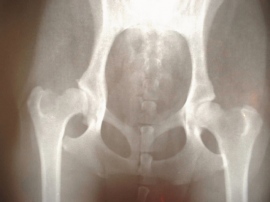

骨粗鬆症は、骨の形成と破壊の新陳代謝バランスが崩れることで、骨強度が低下する疾患。骨折のリスクが高まり、ぶつかったり低所から落ちたりするだけで骨折することもある。生活機能を低下させるだけでなく、生命予後にも悪影響を与えることが明らかになっている。日本骨粗鬆症学会の「骨粗鬆症の予防と治療ガイドライン」(2015年版)によると、日本の骨粗鬆症患者数は男性300万人、女性980万人と推計されており、世界的に見れば骨粗鬆症が原因の骨折は50歳以上の女性3人に1人、男性5人に1人で発生している。患者数の増加に伴い骨粗鬆症治療薬の市場も伸びていて、調査会社の富士経済が14年に発表したレポートによると、市場規模は22年には13年に比べ47%増加の3204億円に達するとのこと。

こうしたなか、マーケティングリサーチを提供する総合企画センター大阪は、骨粗鬆症治療での薬剤処方状況や現場での薬剤の評価を明らかにすることを目的として、骨粗鬆症患者50人以上を担当し、副甲状腺ホルモン(PTH)製剤または抗体製剤を処方しているドクター30名に対してインタビュー調査を実施した。同調査結果によれば、薬物治療を行っている患者6753人においての各薬剤処方の割合は、「活性型ビタミンD3製剤」(カルシウムの吸収を助ける)が65.4%で最も高く、以下「ビスホスホネート(BP)製剤」(破骨細胞の活動を阻害)(54.8%)、「SERM」(女性ホルモンの量を調整)(21.5%)、「プラリア」(破骨細胞の分化を抑制)(17.9%)、「PTH製剤」(骨を作る細胞の働きを高める)(7.7%)の順となった。

診療科別では、整形外科で「活性型ビタミンD3製剤」が約8割(76.9%)と高い割合だったほか「BP製剤」が約半数(51.3%)となった。一方、内科・婦人科では「BP製剤」が6割強(60.9%)で最も多く、「活性型ビタミンD3 製剤」については半数以下(45.1%)となっている。各薬剤の評価についての有効性では「フォルテオ」(PTH製剤)が最も高く、続いて「テリボン」(PTH製剤)、「プラリア」の順となっている。一方、「活性型ビタミンD3製剤」と「SERM」はやや評価が低かった。安全性については「活性型ビタミンD3製剤」や「SERM」の評価が高く、「テリボン」の評価が最も低い結果となった。